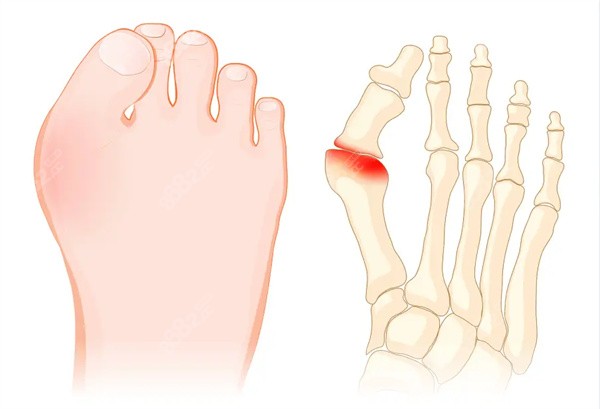

哈嘍,各位被大腳骨(也就是拇外翻)困擾的朋友們!是不是總在為選鞋發(fā)愁,覺得腳型不好看,甚至走路久了就疼?前些天和閨蜜聊天,她還在吐槽因為腳骨突出,好多漂亮的鞋子都只能看看。

核心頭牌:小切口小創(chuàng)口技術(shù):這是蘇醫(yī)生較大的招牌!他做手術(shù)的切口非常小,普遍只有3-5毫米,較大的也就1厘米左右。

你可以想象一下,傳統(tǒng)的“大刀闊斧”變成現(xiàn)在的“精細(xì)雕刻”,對周圍組織的傷害降到較低,這直接關(guān)系到后面修復(fù)得快不快、疼不疼。